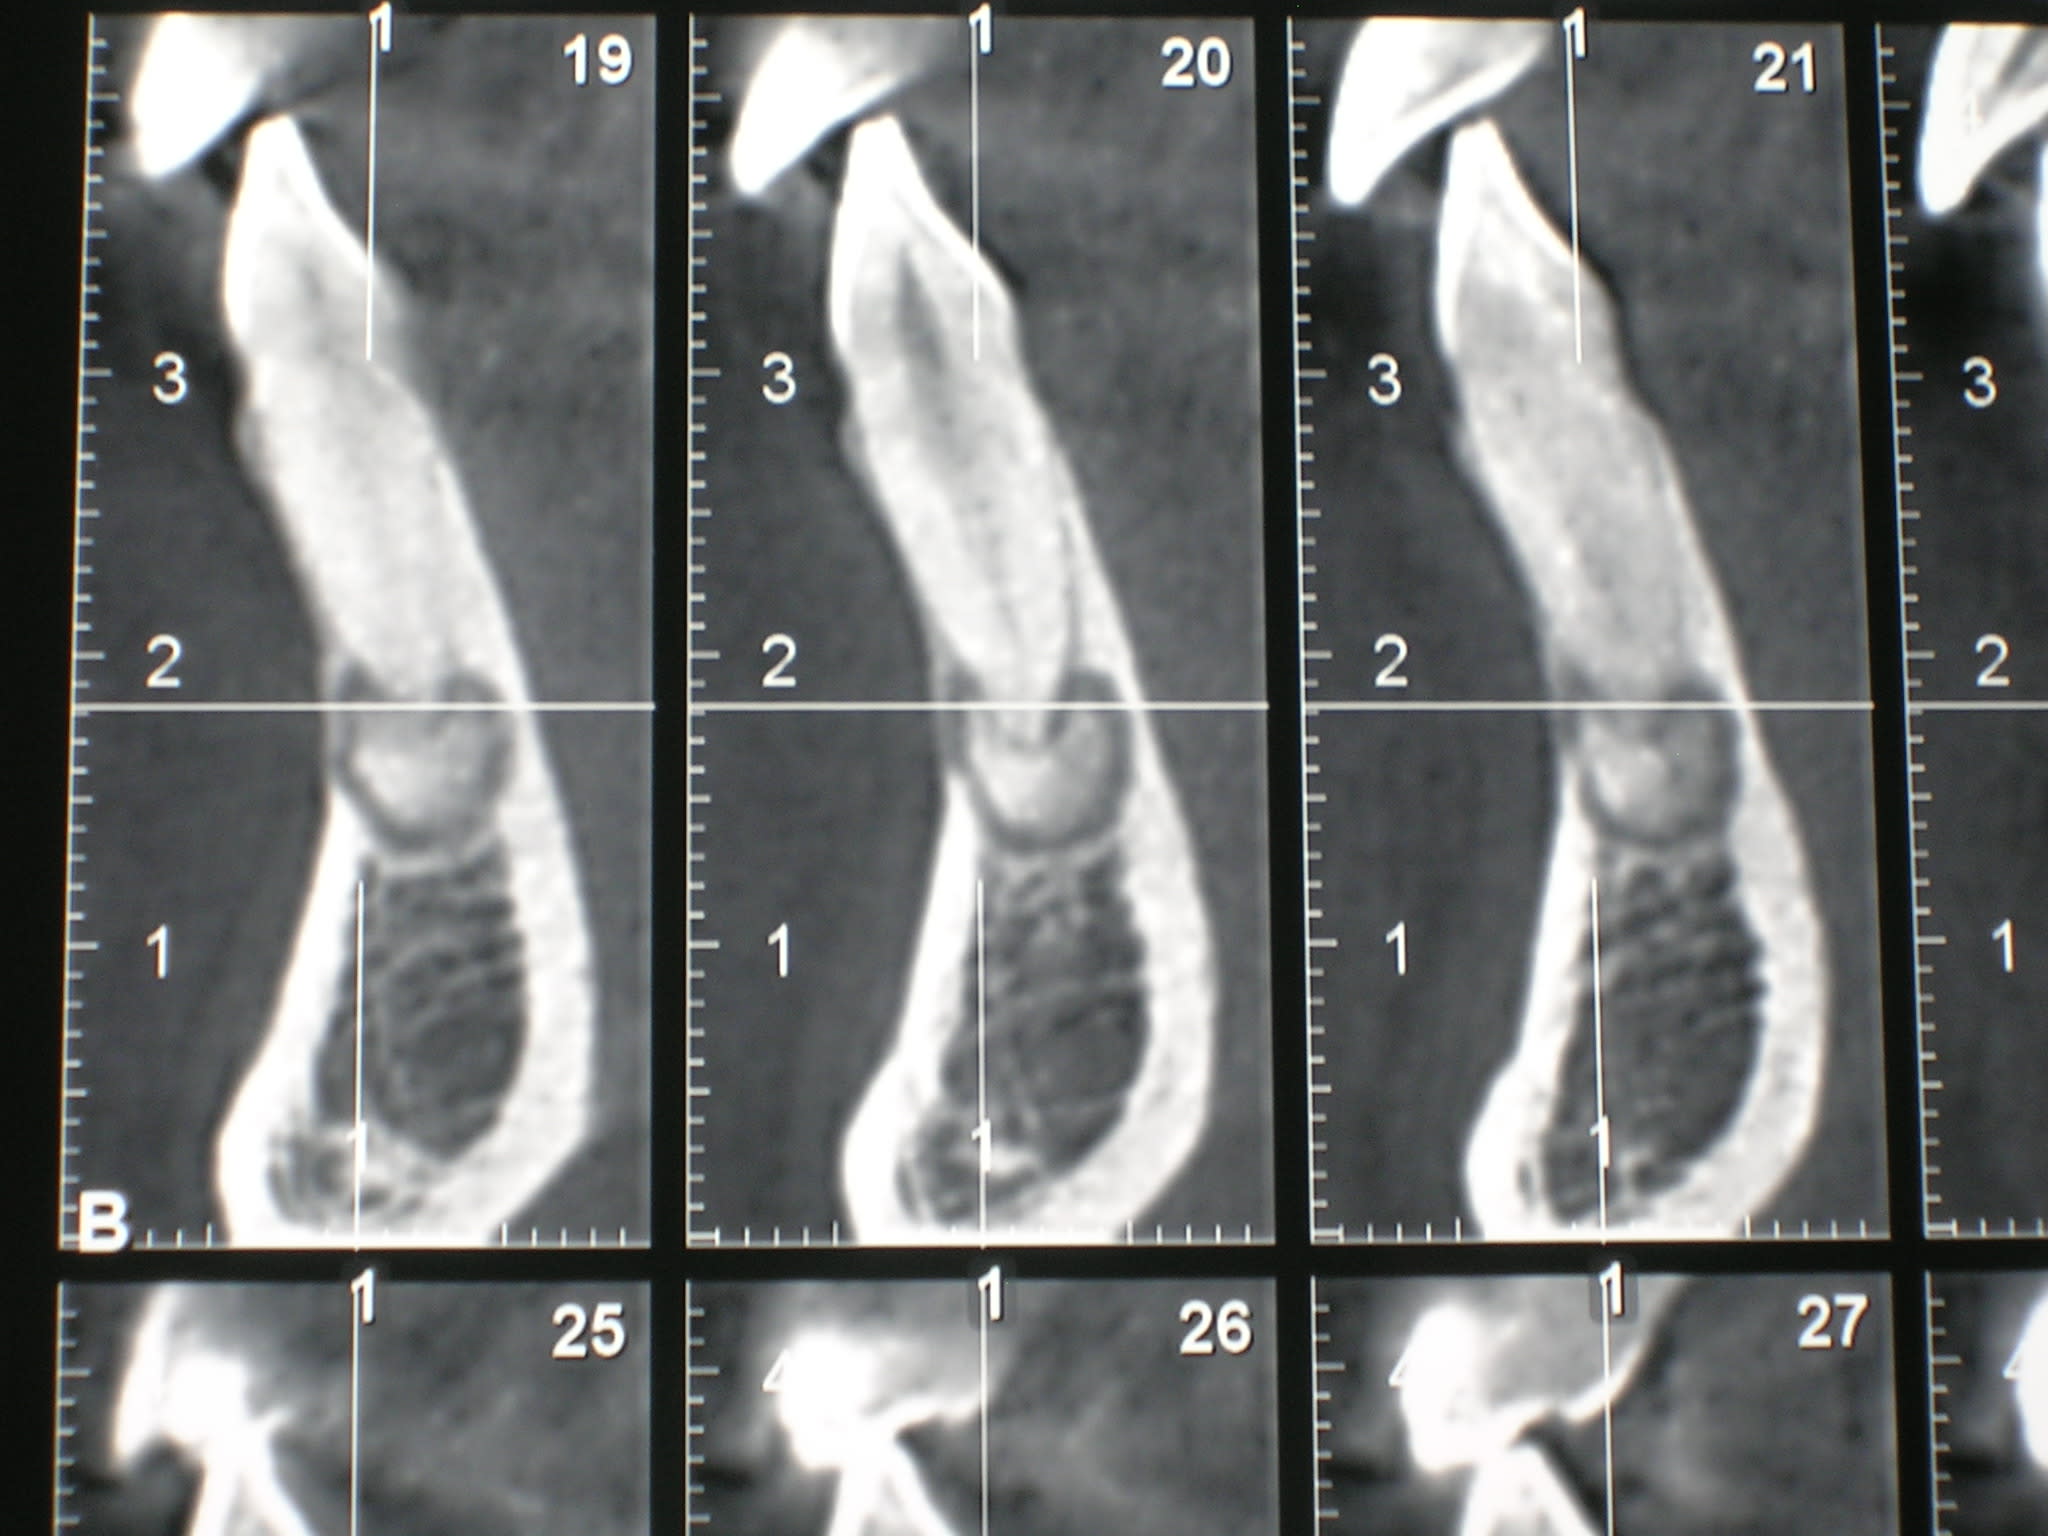

J'ai fait réaliser un CBT et le radiologue me parle de cimentoblastome (je pense cementoblastome).

A la rétro alvéolaire on a une image de calcification apicale.